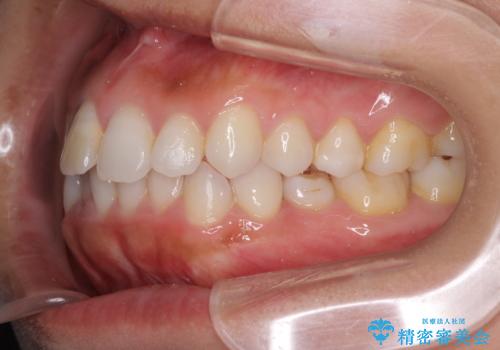

- 上下の前歯のデコボコと奥歯の反対咬合を気にして来院された患者様です。

インビザラインを用い、上下顎ともにIPR(歯と歯の間を削る)により叢生を改善することとしました。

奥歯の反対咬合は、骨格に由来するものであるため、改善できるところまで改善していくこととしました。